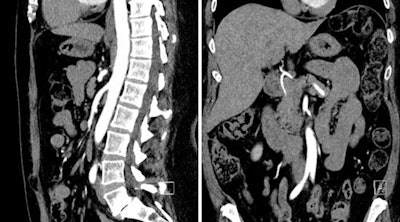

The investigators from Northwestern University examined 20 patients referred for abdominopelvic CTA using a novel protocol that substantially reduced both radiation dose and contrast. Even with a dose as low as 3 mSv of radiation and 15 mL of iodinated contrast, the results showed no reduction in objective or subjective image quality using the technique.

"We showed that abdominal CT using an ultralow-dose contrast protocol is clinically and technically feasible, and we can achieve good image quality and homogeneous attenuation across vascular levels," said Dr. Faezeh Sodagari, who received an RSNA Student Travel Stipend Award for the CTA abstract.

"In our institution, we have developed a protocol which reduces the amount of contrast, and we wanted to know if an ultralow contrast media protocol ... has acceptable image quality and provides homogeneous attenuation across vascular levels in abdominal CT angiography," she said. "So we were very interested in this new study that recruited average-sized patients referred for abdominopelvic CT who received this new protocol, and we excluded patients with vascular thrombosis."

The study evaluated the homogeneity of vascular enhancement as well as image quality in 20 patients (mean age, 67 years) who underwent low-contrast-dose CTA at low kV.

The acquisition protocol on a third-generation dual-source CT scanner (Somatom Force, Siemens Healthineers) included 0.6-mm collimation, 2.8 pitch (range, 1.6-3.2), tube current set by automatic exposure control, a scan duration of 0.8 seconds, and tube voltage of 80/90 kV with automatic tube voltage selection.

Before imaging, 15 mL to 30 mL of iodinated contrast (mean, 20.1 mL) diluted with saline was administered. Bolus tracking software triggered scan initiation at 130 HU in the abdominal aorta, and images were reconstructed using advanced modeled iterative reconstruction (ADMIRE, Siemens).

Ultralow-dose contrast CTA with low radiation dose is both technically and clinically feasible, producing high image quality and homogeneous attenuation, Sodagari concluded.

The study shows the potential for reducing the contrast dose to as low as 15 mL for high-pitch abdominopelvic CT angiography at 80 kV. This may have clinical implications in abdominopelvic CT angiography, particularly in patients with renal impairment.